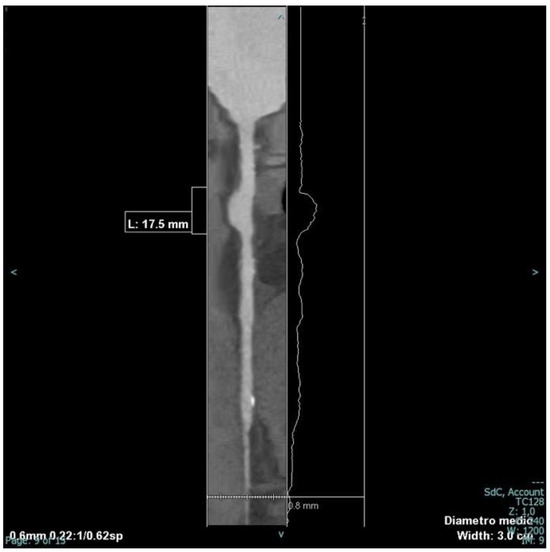

2.2. Examinations

2.3. Management